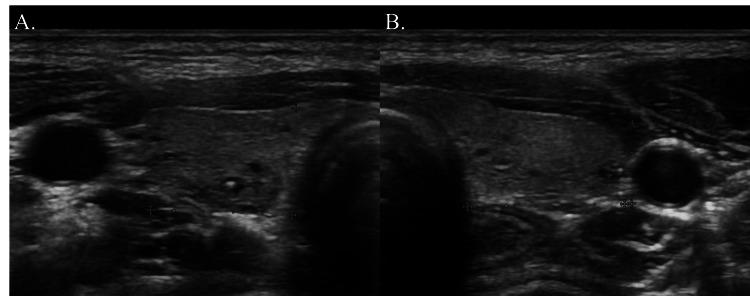

一名青春期女孩因原发性甲状旁腺功能减退症导致严重低钙血症和QT间期延长并伴有短暂意识丧失。

Transient Loss of Consciousness Associated With Severe Hypocalcemia and QT Prolongation Due to Primary Hypoparathyroidism in an Adolescent Girl.

As hypocalcemia is uncommon, serum calcium levels are not routinely measured in many emergency medicine clinics. We report a case of an adolescent girl with a transient loss of consciousness due to hypocalcemia. A 13-year-old healthy girl had a syncopal episode complicated with numbness in the extremities. On admission, she was fully conscious, but hypocalcemia and QT prolongation were noted. After careful consideration of the possible etiologies, the patient was diagnosed with acquired QT prolongation due to primary hypoparathyroidism. The patient's serum calcium levels were controlled by activated vitamin D and calcium supplementation. Primary hypoparathyroidism-associated hypocalcemia can cause QT prolongation and neurological complications, even in previously healthy adolescents.

摘要

由于低钙血症并不常见,许多急诊医学诊所并不常规检测血清钙水平。我们报告一例因低钙血症导致短暂意识丧失的青春期女孩病例。一名13岁健康女孩发生晕厥,伴有四肢麻木。入院时,她意识清醒,但发现有低钙血症和QT间期延长。在仔细考虑可能的病因后,患者被诊断为原发性甲状旁腺功能减退所致的获得性QT间期延长。通过活性维生素D和补钙控制患者的血清钙水平。原发性甲状旁腺功能减退相关的低钙血症即使在既往健康的青少年中也可导致QT间期延长和神经并发症。